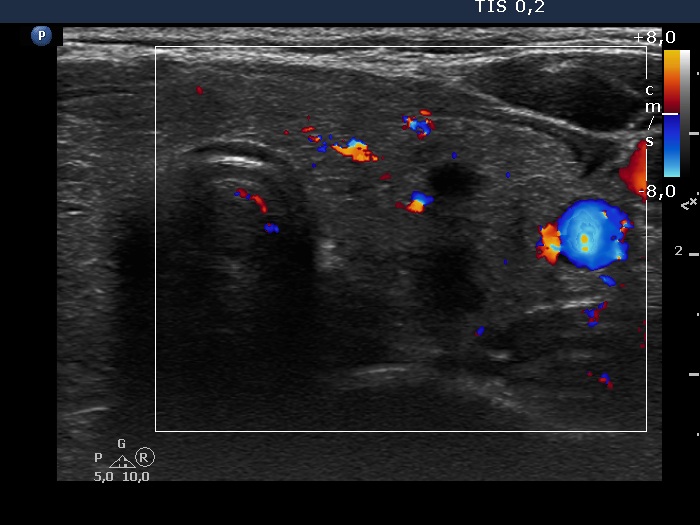

Consecutive patients with the final diagnosis of Hashimoto's thyroiditis - case 52 (1172) (ultrasonographic picture 8)

Left lobe, transverse scan, color Doppler mode. The vascularization is average.